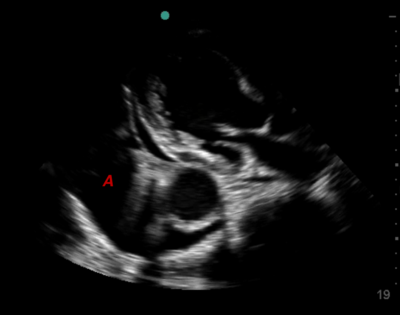

Area B is... ?

Image:

31846c28-3f62-43fa-af6a-8bc2602983ec (image/png)

Pericardial Effusion

Pleural Effusion